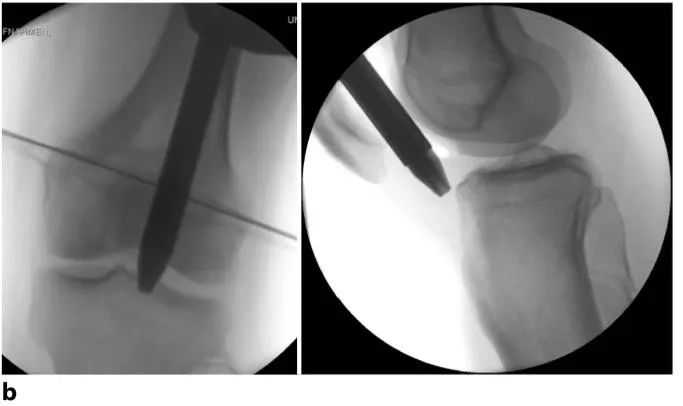

Рисунок 8а. Рукоятка в сборе вводится под надколенник через надколенник-бедренный сустав в направлении желаемой точки входа на большеберцовой кости (Рисунок 9). В большинстве случаев во время введения инструмента надколенник слегка смещается медиально или латерально. Канавка в надколенниково-бедренном суставе обычно автоматически направляет иглу троакара в правильное положение.

Рис. 8b. Положение было подтверждено в обеих плоскостях с помощью рентгеноскопии и при необходимости скорректировано. Затем иглу троакара заменяют пористым проводником, который проходит через центральное отверстие проводника и кончик которого вводится в проксимальный метафиз большеберцовой кости для обеспечения правильного положения.